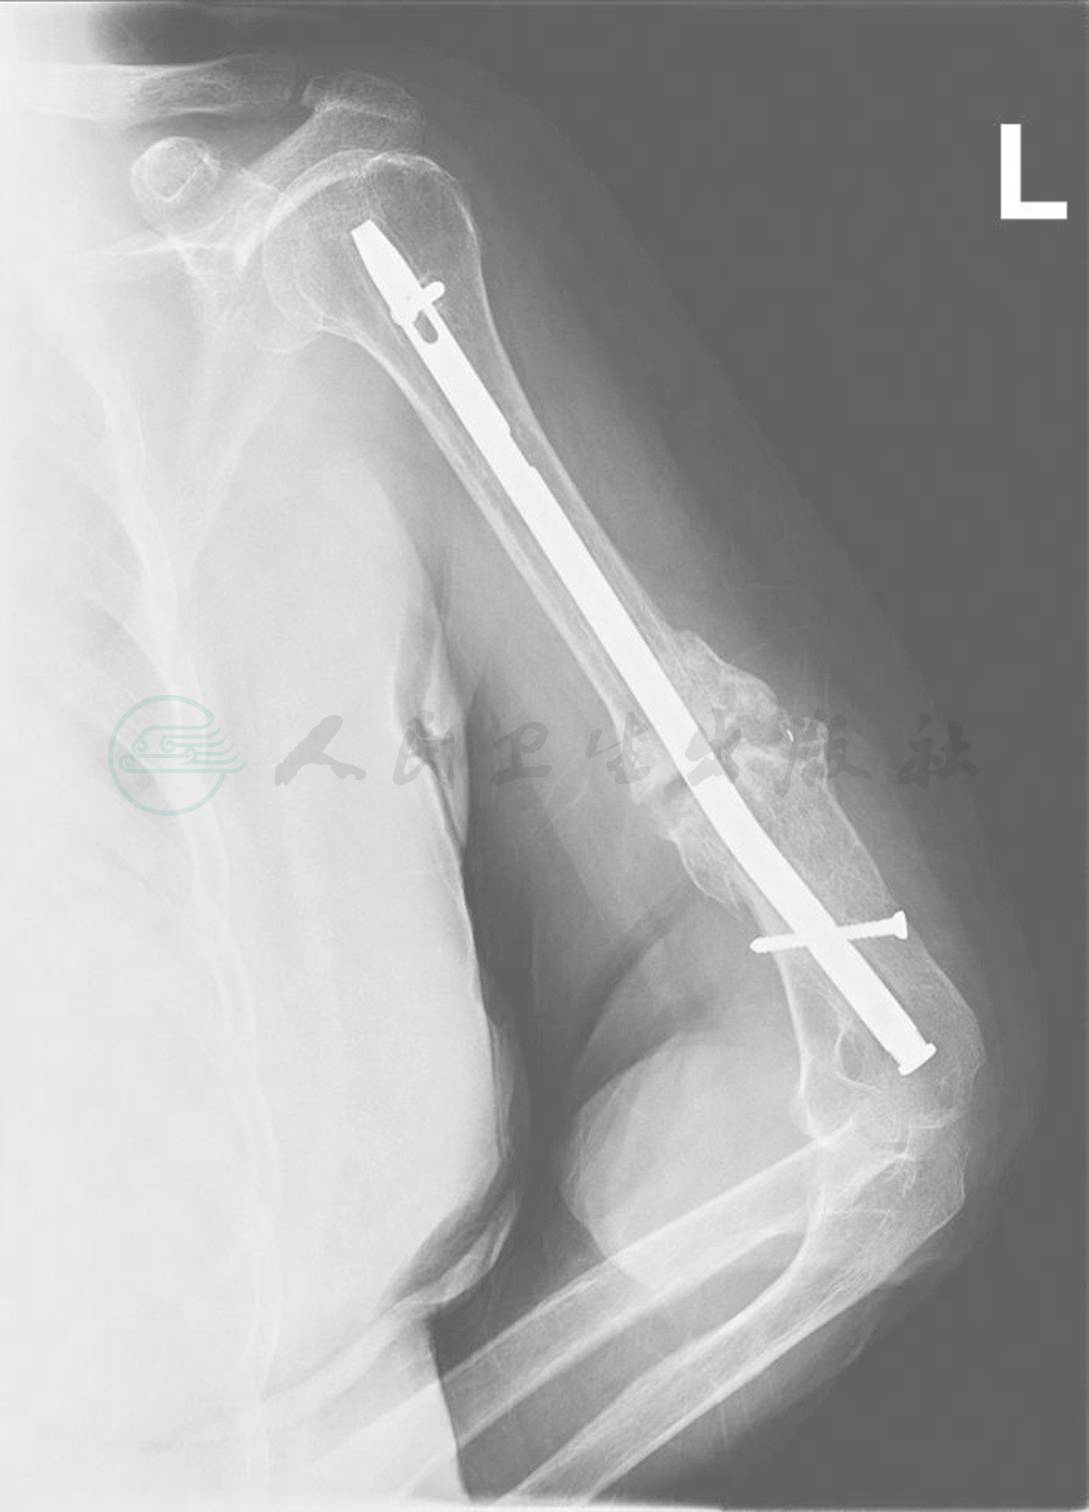

图4 股骨干开放性骨折髓内钉内固定后骨不连患者

A.患者术前X线片,可见患者股骨为开放性粉碎骨折;B.采取髓内钉内固定术后X线片;C.术后13个月X线片,骨折线仍清晰可见,另可见远端骨块不包含峡部,髓腔较为宽大,稳定性欠佳;D-G.术中在远端骨折块偏近端置入三枚阻挡螺钉,缩小髓腔宽度;H.术后X线片。